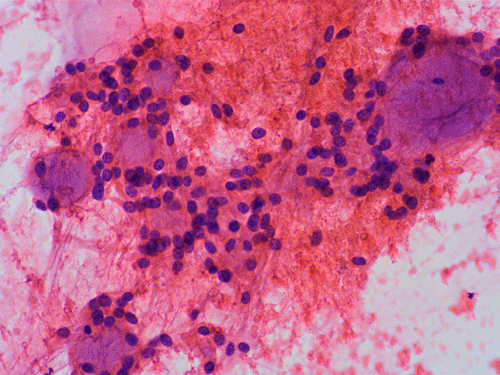

On cytologic preparations, there are clumps of tissue that do not smear out well (Panel A). On higher magnification, these tissue clusters are composed of large blobs of bluish, acellular, mucoid material admixed with cells with relatively uniform, bland nuclei and small amount of cytoplasm (Panel B). In the less tightly packed areas, the long cytoplasmic processes of the cells can be well appreciated (Panel C). These long processes are highly suggestive of a glial neoplasm. On frozen sections, the lesion is composed of multiple blobs of bluish, mucoid material surrounded by tumor cells (Panel D and E). Features of the paraffin sections are not that much different from that of the frozen sections (Panel F G H).

Comment: The nuclear feature is often better appreciated in cytologic preparation than frozen sections. This is well illustrated in this example.